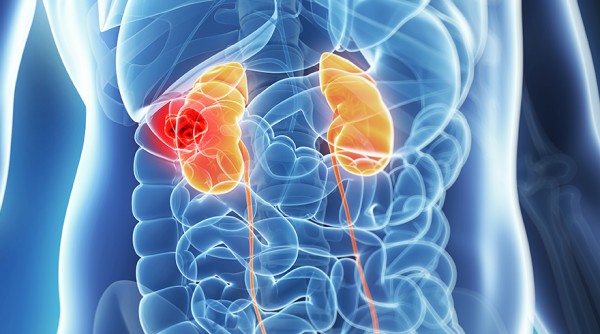

"I had an excellent experience at the urology clinic. The staff was very friendly and professional, and the doctor was knowledgeable and thorough in their examination. I received the care and attention I needed to address my urological concerns, and I highly recommend this clinic to anyone seeking quality